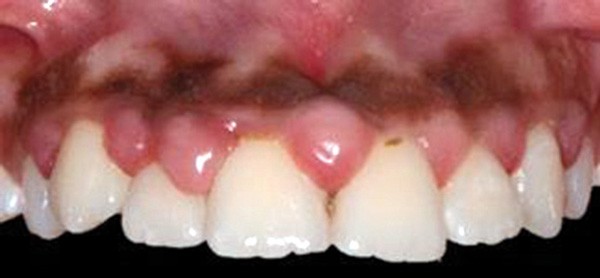

Traitement ultra-conservateur des taches de l’émail : bilan avec 5 ans de recul

Les auteurs de cette conférence nous proposent un algorithme pour résoudre le problème des taches blanches de l’émail. Ces techniques sont désormais utilisées avec succès depuis 10 ans. Tout d’abord il convient souvent de réaliser un éclaircissement préalable : celui-ci diminue le contraste entre la tache et le reste de la dent. Ensuite, avant de poser le champ opératoire, il faut choisir la teinte du composite qui sera nécessaire à la fin du traitement. Un sablage/fraisage des taches les plus profondes est alors réalisé, en fonction de la profondeur de la tache. Vient alors l’infiltration ou masquage optique, qui fonctionne sur les taches blanches : on passe une solution d’acide chlorhydrique, puis une solution d’hypochlorite de sodium, et si la tache est devenue blanche alors il est possible de passer à l’infiltration par la résine. Enfin, s’il subsiste une concavité visible, un composite viendra la combler. Le polissage clôt alors le protocole(fig. 11 et 12).